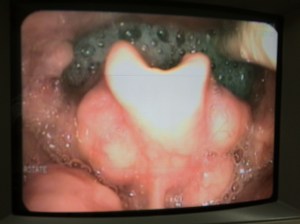

FEES view at the Oropharynx and Laryngopharyx

FEES: Anatomy of the pharynx and larynx (Superior View)

FEES: Interesting case study on the “Rising Tide” presentation